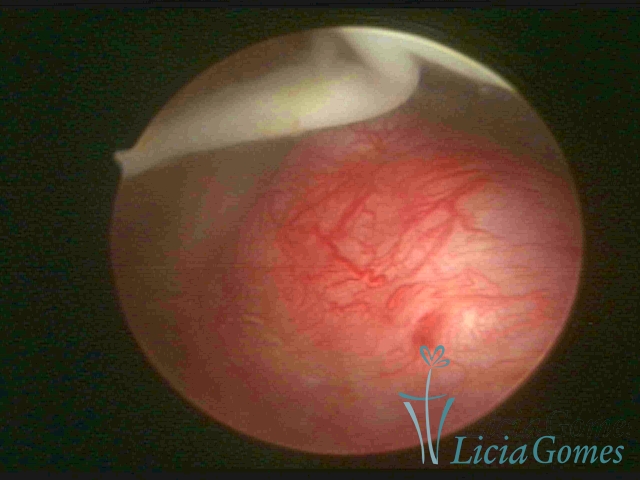

Intact egg cell debris in the uterine cavity